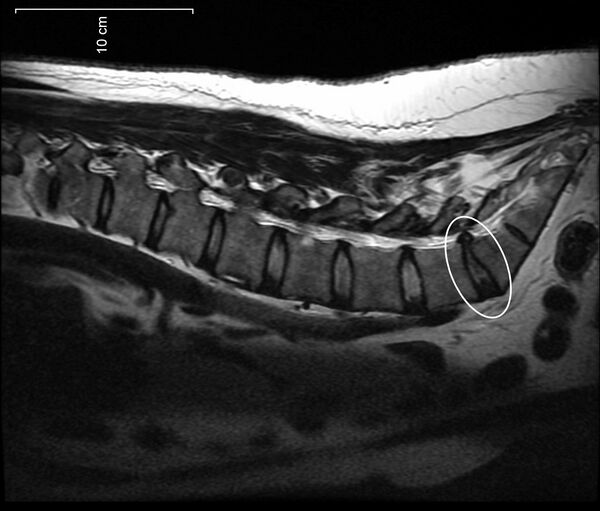

Протру́зия межпозвонкового диска — патологический процесс в позвоночнике, при котором межпозвонковый диск выбухает в позвоночный канал без разрыва фиброзного кольца, возникающего при грыже. Чаще всего локализуется в поясничном и реже — шейном отделах. В клинической практике встречается гораздо чаще, чем экструзия.

При протрузии межпозвонкового диска фиброзное кольцо сохраняет целостность, и сдавливание (раздражение) корешков носит интермиттирующий (периодический) характер. Размер выбухания в различных случаях составляет от 1 до 5 мм.